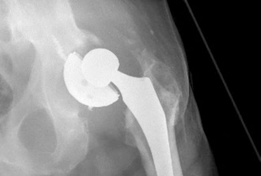

Reconstruction techniques : A hemispherical socket was placed; however, in the presence of posterior wall deficiency, a buttress augment was utilized to support the socket. The cup was fixed with multiple screws, and demineralized bone matrix was placed behind the acetabulum. The augment and the acetabular components were adjoined with the use of cement (Figs. 19.25 and 19.26).

Challenges and solutions: Posterior wall deficiency was resolved with tantalum trabecular metal buttress augmentation of the hemispherical cup.

Thorough description of decision-making, including the reason for the final decision: Acetabular reaming revealed sufficient bone stock such that it was decided to avoid further bone loss associated with reaming to accommodate a jumbo-sized cup. It was decided to address posterior wall deficiency separately with a posterior buttress. A porous-coated multihole tantalum cup was selected as it was anticipated; multiple points of fixation would be needed to secure the cup. It was decided that porous tantalum offered the best potential for bone ingrowth and reduced chance of periprosthetic infection. Structural allograft was avoided due to an increased risk of recurrent infection and associated risk of bone resorption and collapse.